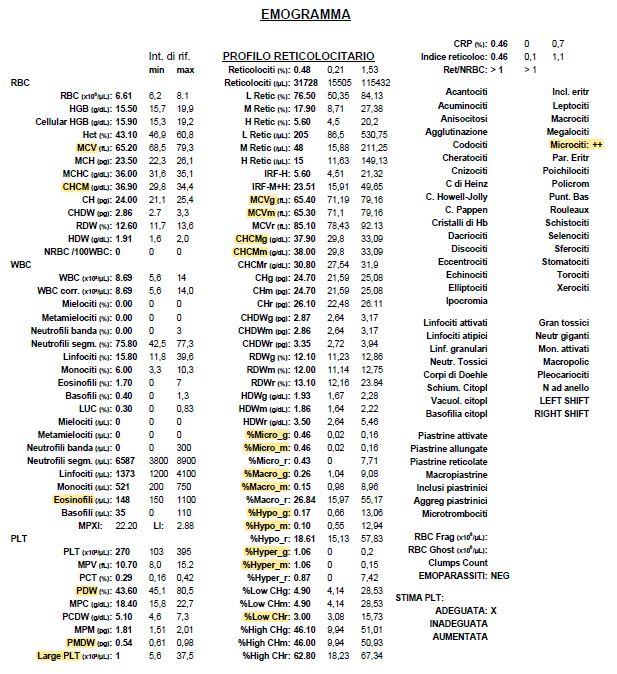

Vorrei chiedere, se possibile, il parere di un veterinario riguardo a degli esami del sangue fatti recentemente ad un cane di piccola taglia. Razza meticcia. Peso circa 9kg. Anni 9.

Chiedo qui perchè ho ricevuto gli esami per email, ma purtroppo è veramente difficile contattare i dottori telefonicamente, spero di passare presso l’istituto settimana prossima. Nel frattempo chiedo cortesemente consigli, dato che ci sono valori che forse non sono entro la norma.

Il cagnolino è stato portato in clinica perchè improvvisamente sembrava affaticato, aveva bisogno di sedersi durante la normale passeggiata. mentre solitamente è abituato a correre e giocare per tutto il tempo.

Specifico che ho evidenziato io i valori che , secondo me, risultano sbagliati. Ovviamente non ho nessuna competenza in materia.